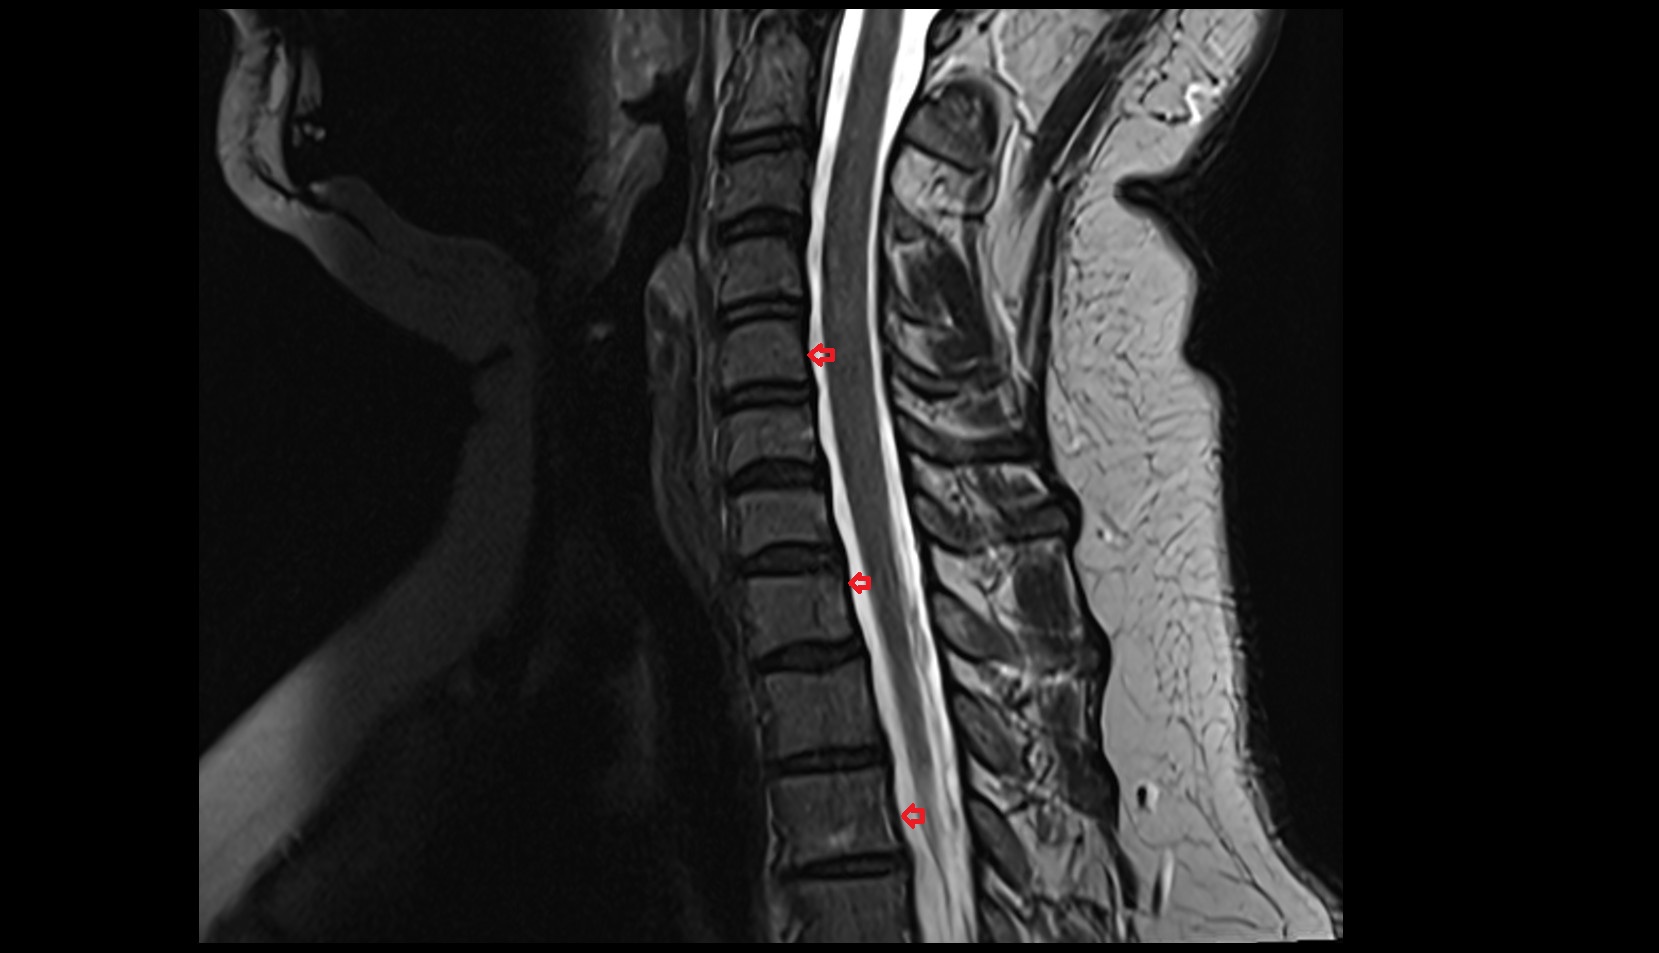

- Spinal cord

- subarachnoid space of spinal cord

- Cauda equina

- Conus medullaris